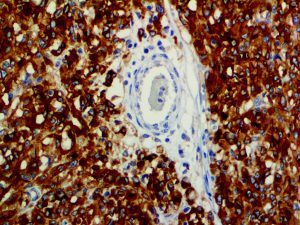

It is the ICU physician who is most likely to witness one of the deadliest manifestations of the abnormal immunological response, the cytokine storm syndrome (CSS). This response is also referred to by some as the cytokine release syndrome (CRS). CSS is characterized by continuous activation and expansion of macrophage and lymphocyte populations, which secrete large amounts of cytokines, causing the cytokine storm. This massive cytokine release is akin to hemophagocytic lymphohistiocytosis (HLH) disease, a syndrome characterized by initial unchecked and persistent activation of cytotoxic T lymphocytes and NK cells.

This activation induces inflammatory monocytes to highly express IL-6, starting a localized and then systemic cascade effect that results in hyperproduction of IL-6, which accelerates the inflammatory process. Because IL-6 also increases vascular permeability, excessive levels cause blood vessels to become very leaky. This, along with clotting factors released from vascular endothelial cells, stimulates the coagulation cascade, resulting in microthrombosis (tiny clots), which leads to ischemia and tissue death of the kidney, intestines, heart, liver, brain and extremities.